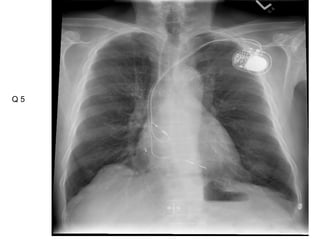

This document contains an ECG test with multiple questions and answers. It discusses cases of: 1. A 60-year-old patient with diabetes, hypertension and chest pain, showing an anterior STEMI with inferior ischemia. 2. A 55-year-old woman with shortness of breath and fatigue, showing a low-voltage ECG and echocardiogram revealing pericardial effusion due to severe hypothyroidism. 3. A 60-year-old with chest pain, showing an anteroseptal STEMI with diffuse ischemia.